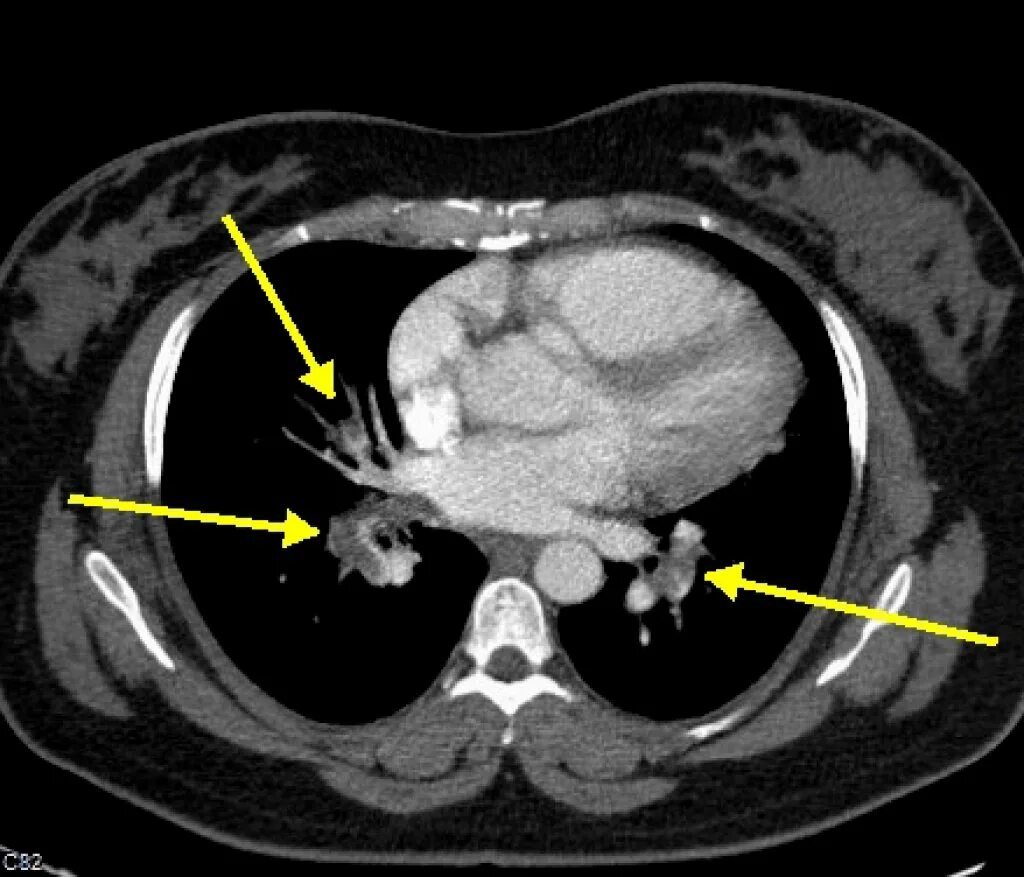

Легочный ствол на кт